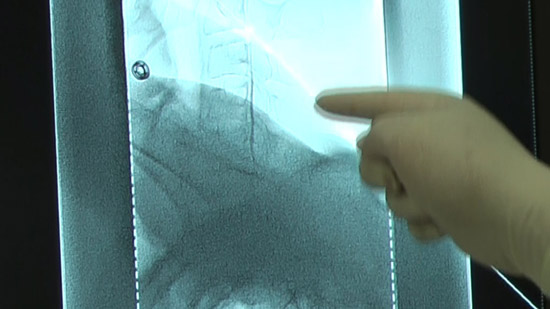

(2)Set the positioning by checking the puncture site along with the image on the radiological screen.

(4)Conduct an epidural puncture by the resistance loss method, checking with the image on the radioscopy screen.

※Inject the contrast medium and check it again. Capture a confirmation image at the same time.

Check with the image on the radioscopy screen.

Check subjective physical condition of patients after 10 cc infusion and capture a projectional image.

Capture projectional images at the end of infusion.